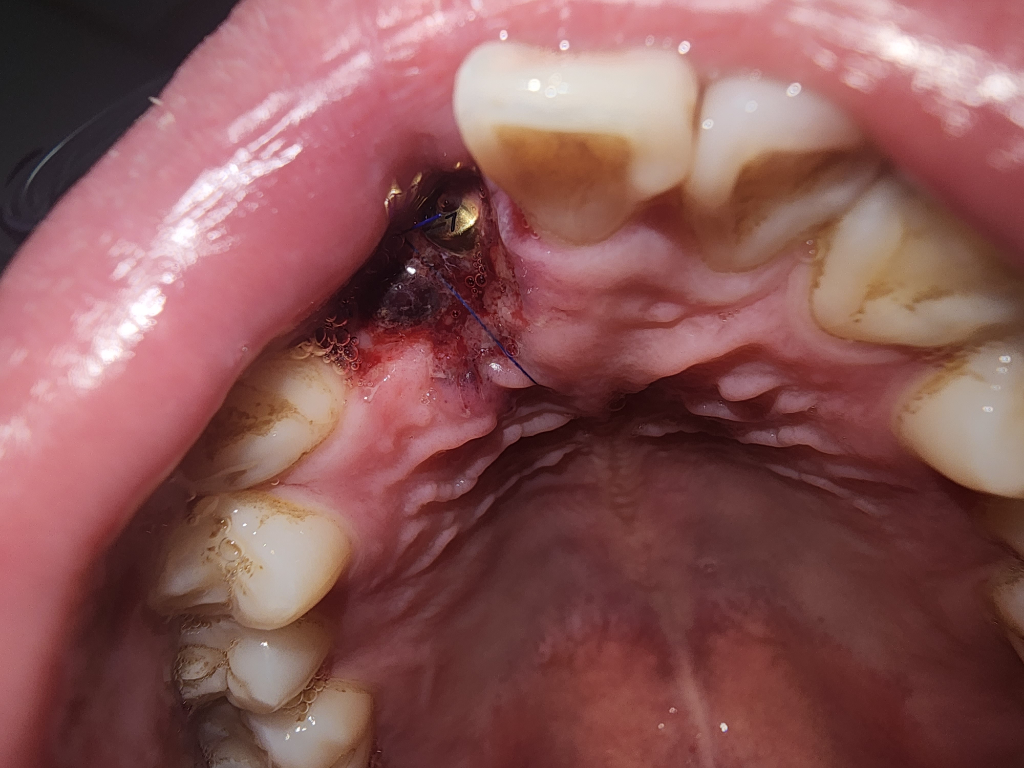

잇몸이식 떼넨 부위 괜찮을까요?

1차 수술로 뼈이식 식립 진행

2차 수술로 금색 기둥? 같은거 박고 잇몸이식수술 진행함

근데 앞니2개 임플란트 진행하는곳 뒤쪽으로 해서 (표시한곳)입천장을 떼서 진행했습니다. 임플란트 부위 지지하는데 지장이 안가는건지 의문이네여

추가로 원본 사진도 올려용